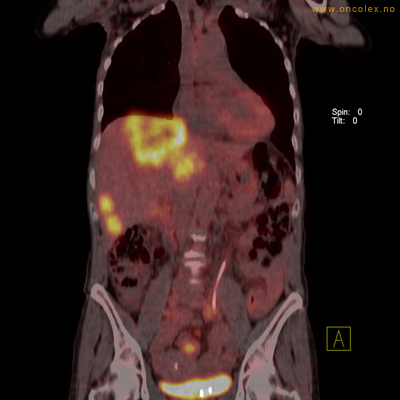

Eksempler på funn

Vev som tar opp mer radioaktivt stoff, synes som hvite områder som lyser opp mer i forhold til annet vev som tar opp mindre sukker.